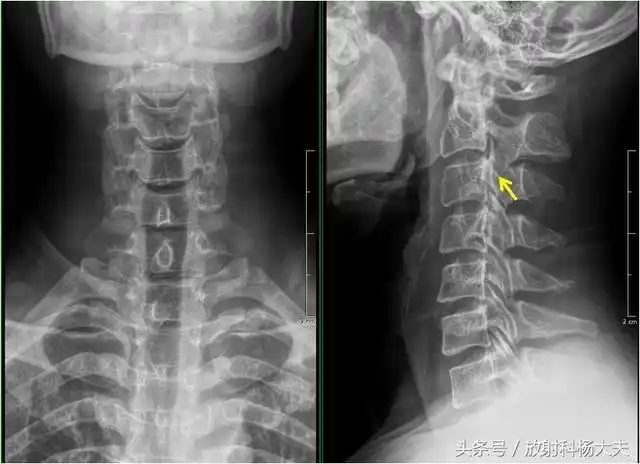

【健康】x线片诊断这种颈椎病,切勿盲目按摩,有可能导致瘫痪

一位经常低头玩手机的女子的颈椎x光照片颈椎曲线变成反弓这危害非常